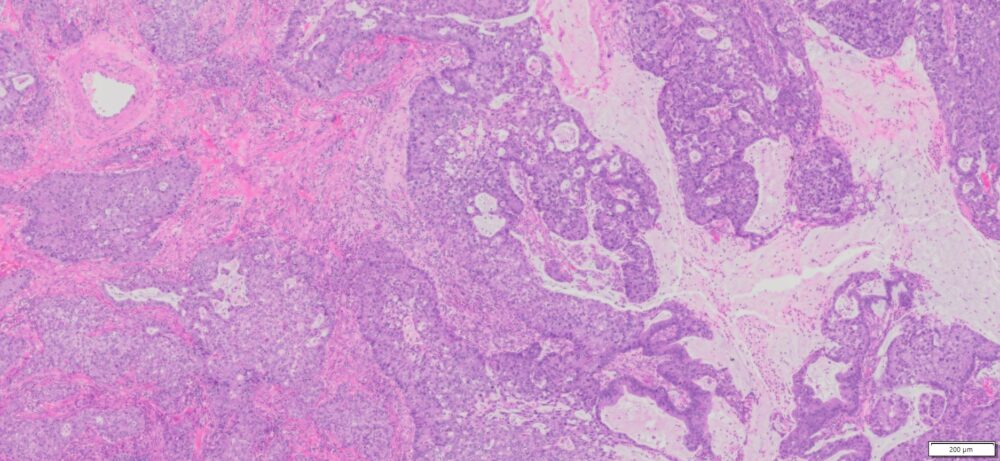

Description

| Organ& Tissue | Pathology Diagnosis | Gender/Age | % Tumor Area | Grade | TMN Stage | Biomarkers |

| Human Cervix | Cervical Adenocarcinoma with mucinous differenciation | Female/38 | 82% | II | NA | P16(+),P40(-),CK5(+), PD-L1 (+) |

Slide Preparation

Human tissue was fixed in formalin immediately after excision and embedded in paraffin. The tissue sections were 5 µm in thickness and mounted each on positively charged glass slides.